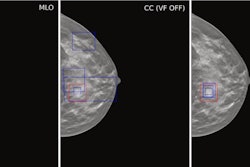

To bridge the knowledge gap, the researchers recruited 186 postmenopausal women (median age, 76 years old) with osteoporosis who were beginning a 12-month romosozumab course. Participants were enrolled at two Belgian clinics and one Italian clinic. Sixty-six participants (35%) were over 80 years old, 30 were over 85 (16%), and most had had a recent (within 2 years) major osteoporotic fracture.

At baseline, based on DEXA scans, their mean lumbar spine T-score was -2.8, mean total hip T-score was -2.4, and femoral neck T-score was -2.7. After 12 months of romosozumab, BMD increased by 9.2% at the lumbar spine and by 3% at the hip. A ≥ 3% BMD increase was observed in 80.4% of participants at the spine, 51% at the hip, and 46% at the femoral neck.